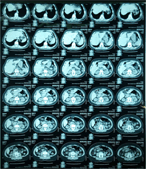

Acute pancreatitis caused by pancreatic ischemia after TEVAR combined with intentional celiac artery coverage and embolization of the branches of the celiac artery

Yohei Kawatani and others

Journal of Surgical Case Reports, Volume 2017, Issue 2, February 2017, rjx029, https://doi.org/10.1093/jscr/rjx029